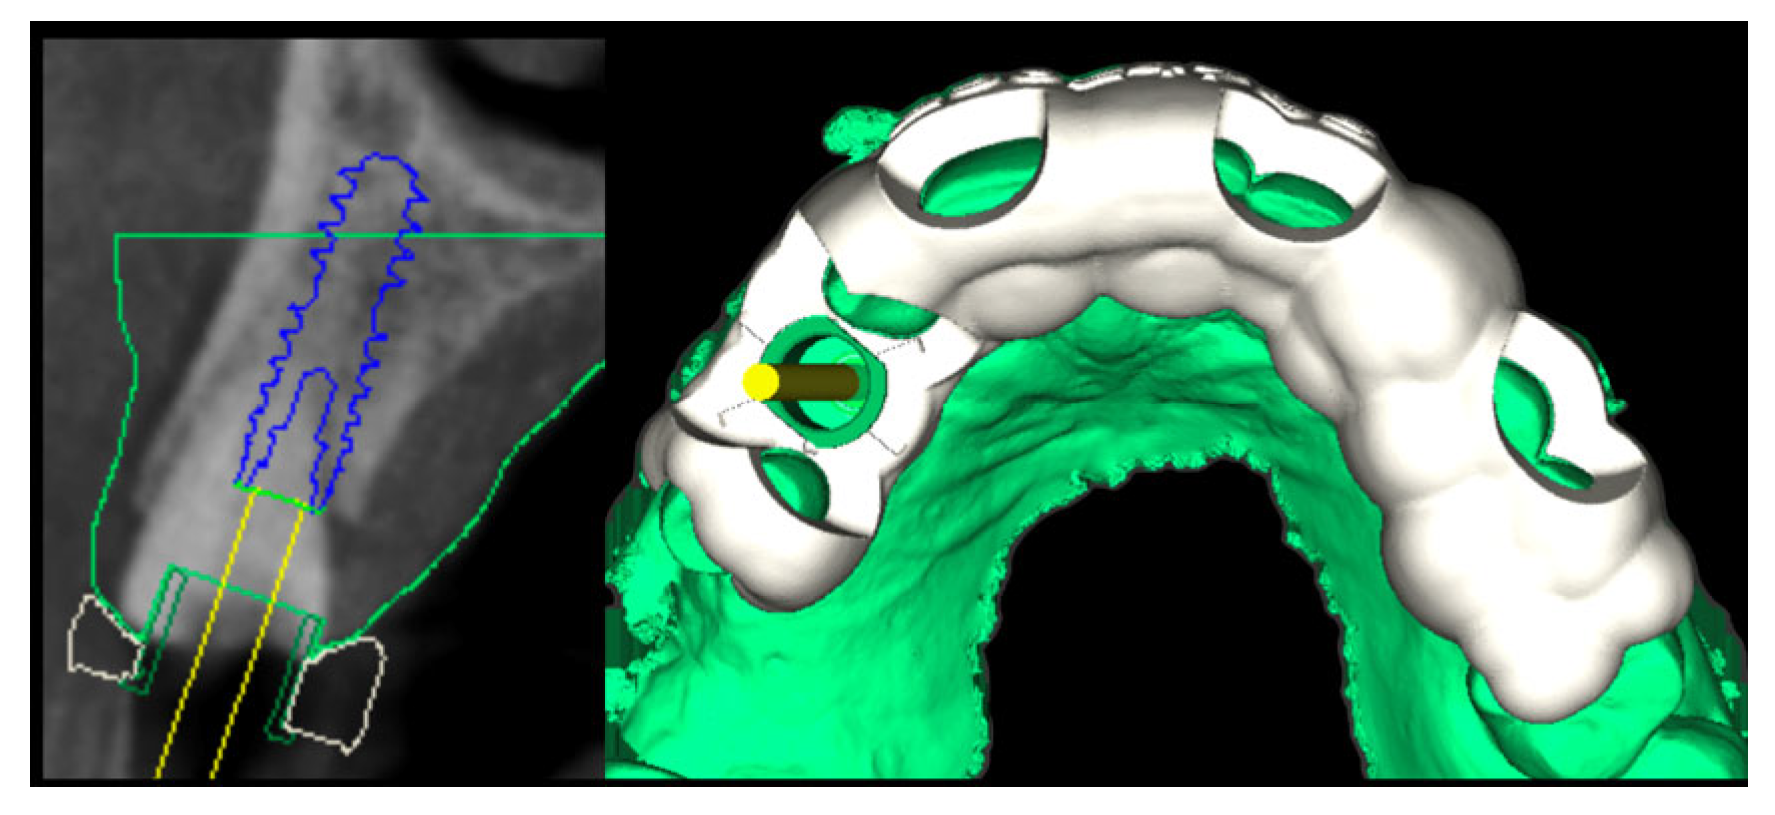

2.2. Surgery